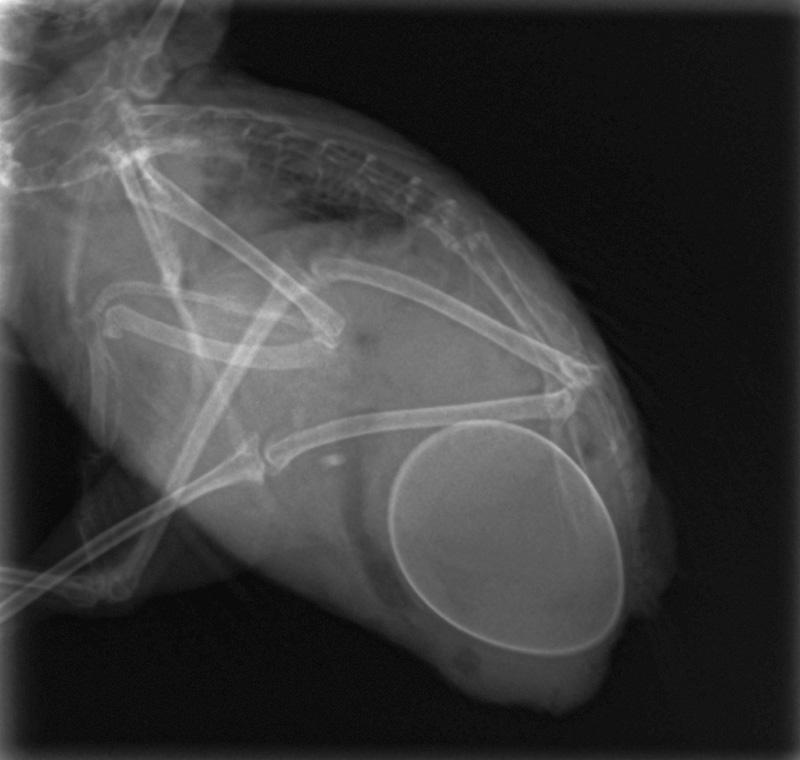

慎重にレントゲンで確認したところ卵があることが確認できました。

レントゲンの写真